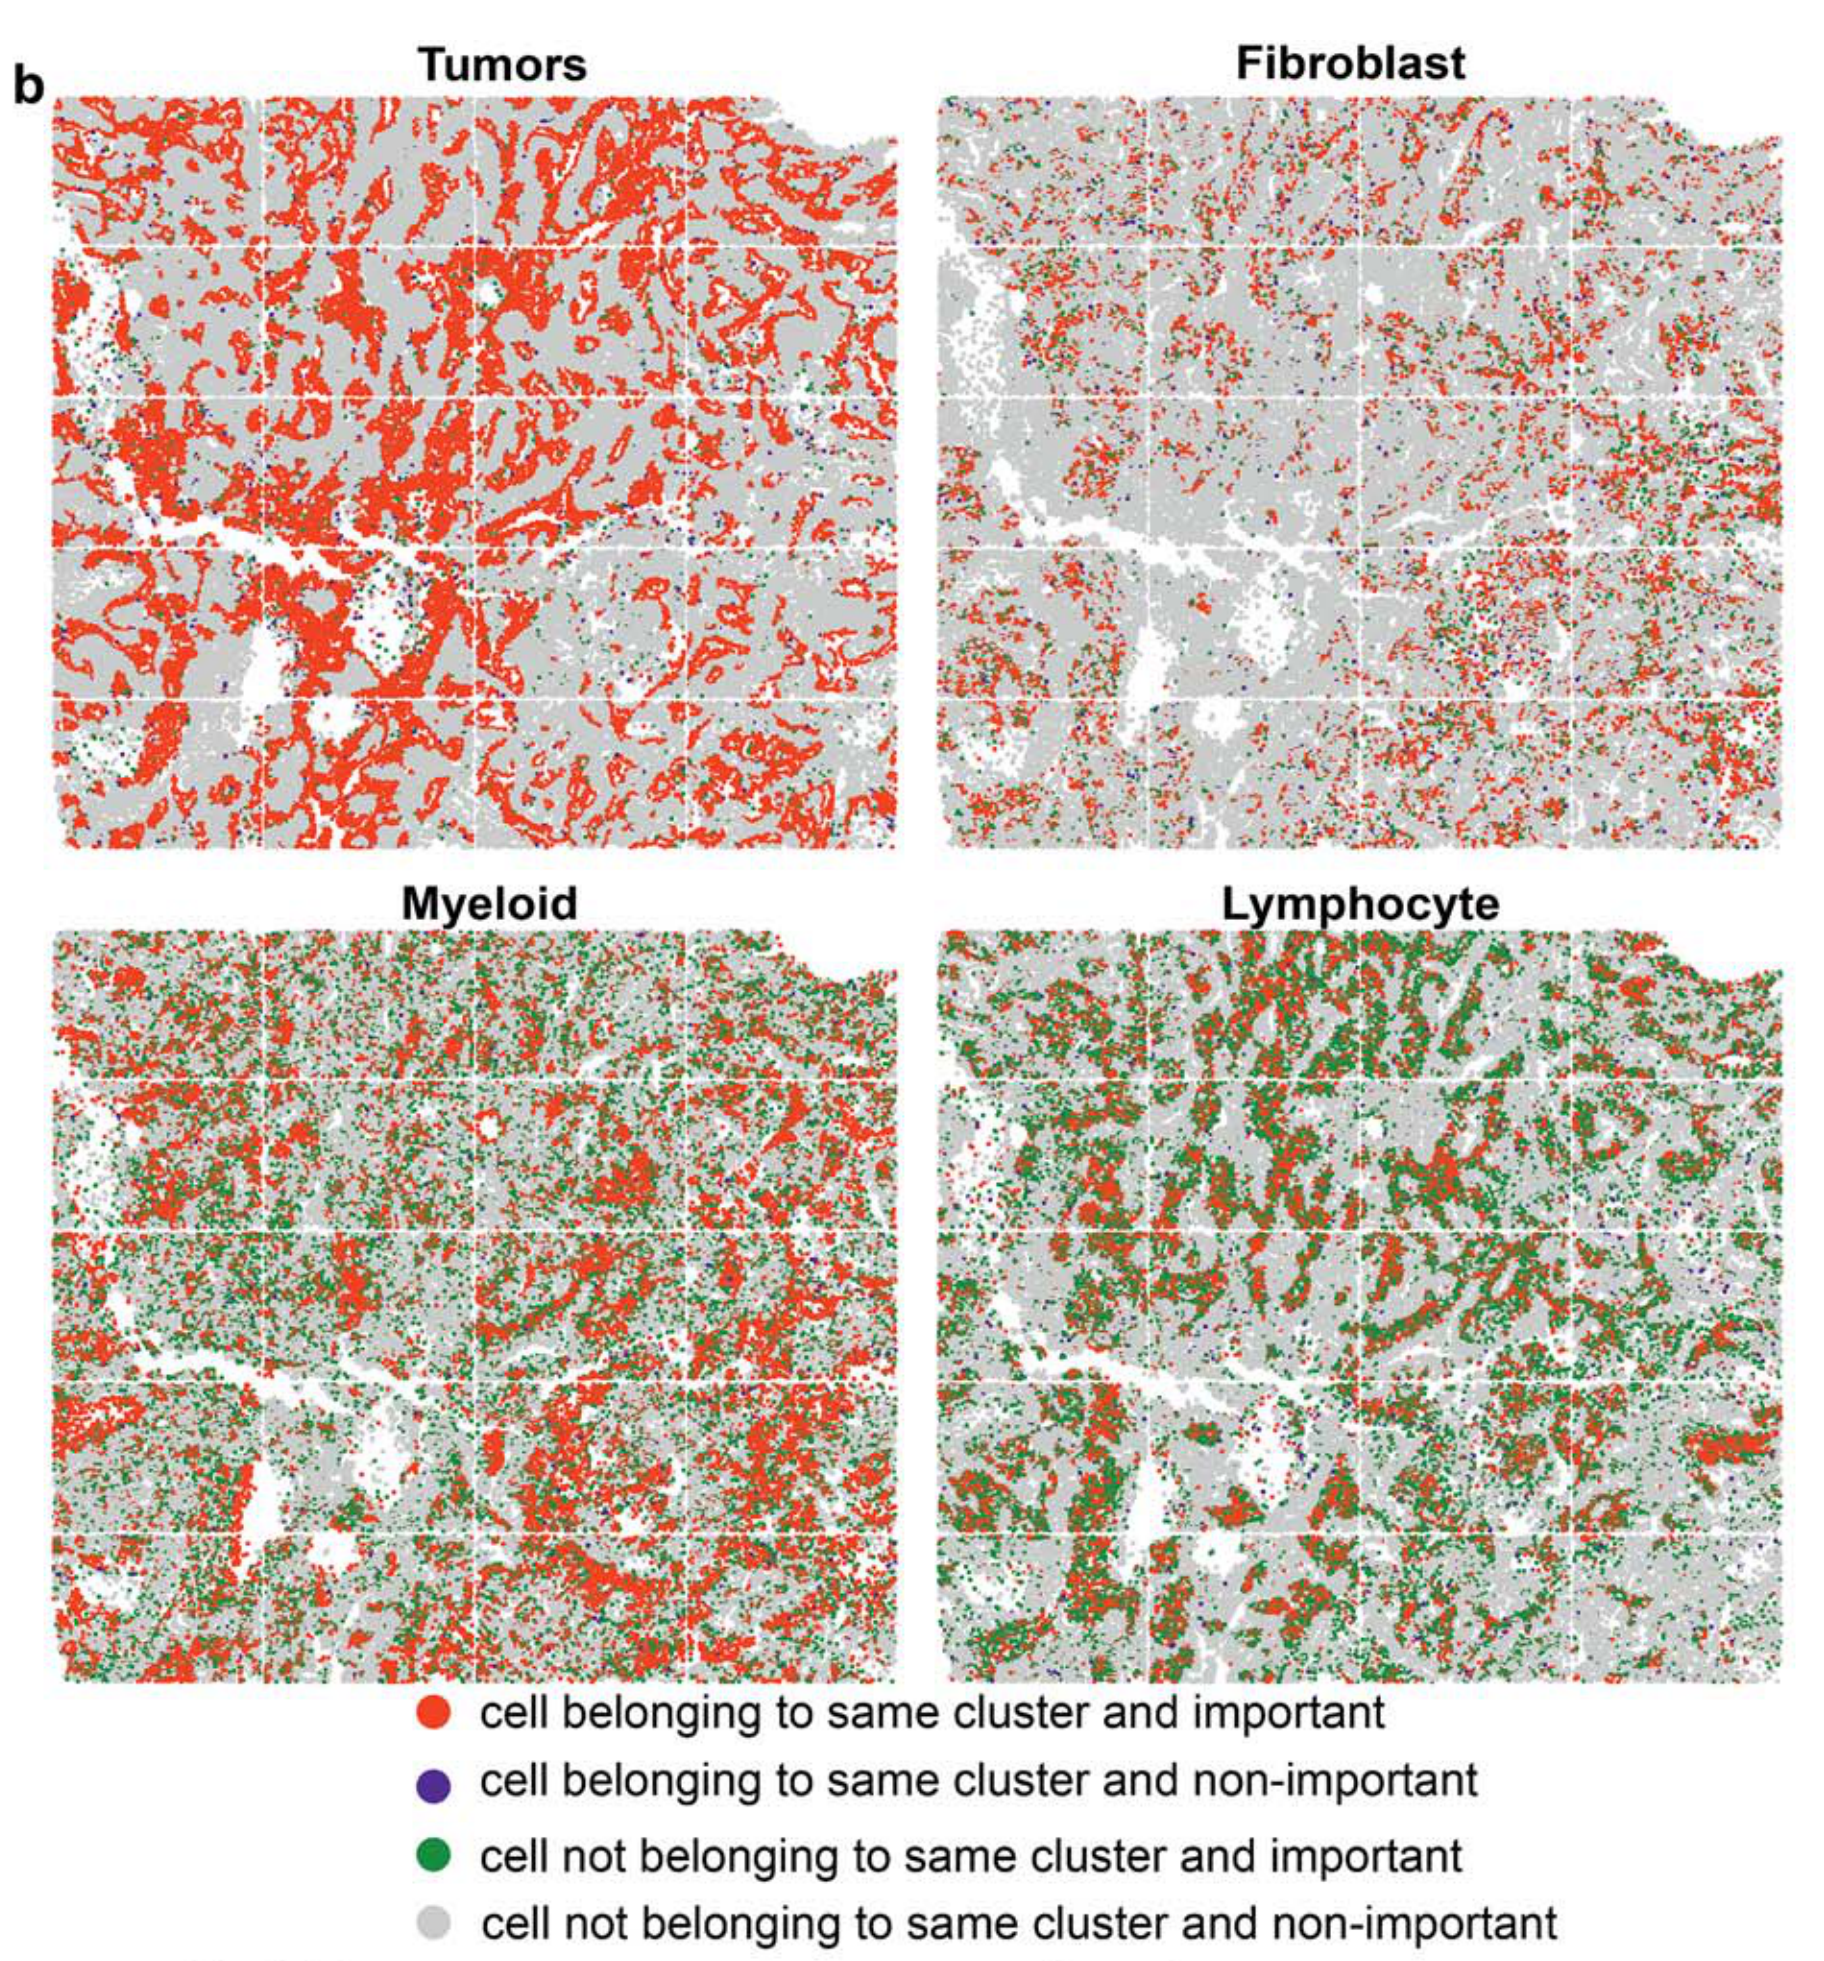

How are specific cell types spatially distributed across tumor tissue sections?